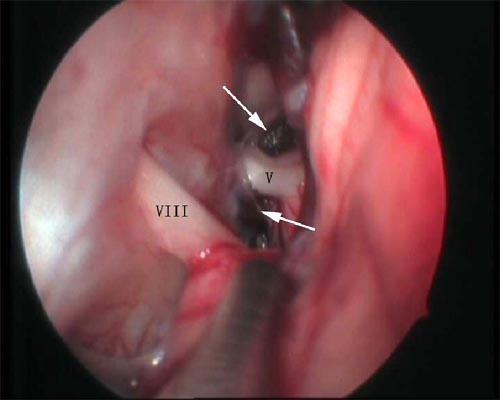

神经内镜辅助下三叉神经微血管减压术

术后示三叉神经(V)与责任血管之间被垫片隔开(↑所示)